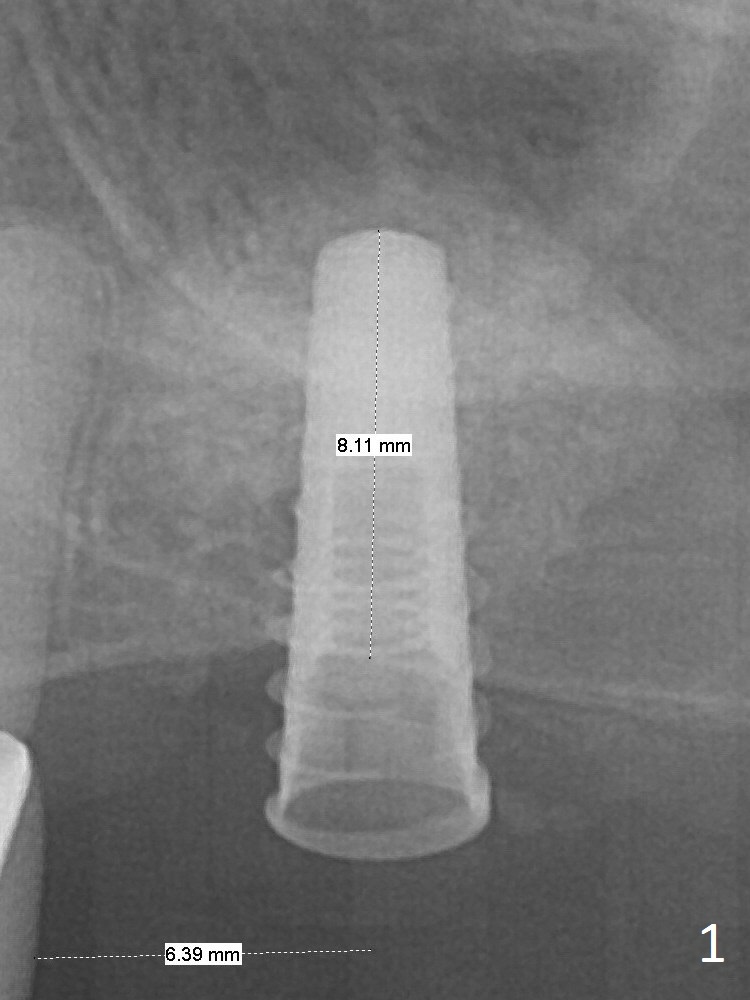

Magic Sinus Lifter is used to elevate the sinus floor for ~ 5 mm, followed by insertion of allograft/Osteogen and 4.0x11 mm dummy implant partially (Fig.1).  With approximately 10% more of graft being placed, a 4.5x9 mm IBS implant is placed with insertion torque of 15 Ncm (Fig.2).  The implant has a tenting effect.  Fig.3 shows a coronal section of the sinus preoperatively.